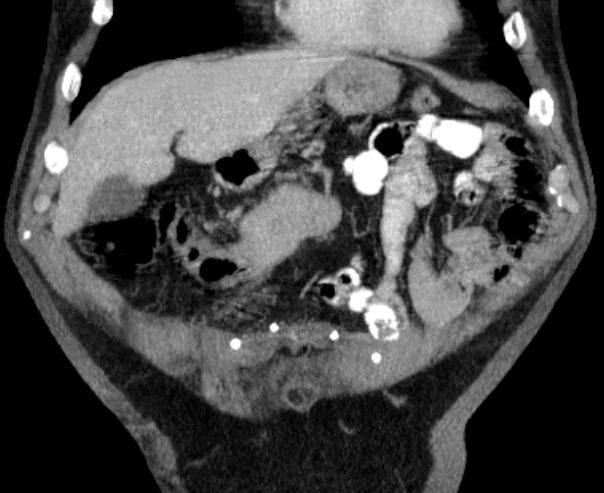

CT: Langstreckige Darmwandveränderungen mit einer hochgradigen Stenose des Colon transversums sowie mit diskreten Verdichtungen in dem umgebenden Gewebe.

Dorsale Harnblasenwandverdickung.

Verkalkungen der Prostata. Keine vergrößerten Lymphknoten![]() |

Operateur: Im Bereich des Quercolons, näher zur rechten Colonflexur, findet sich ein mannsfaustgroßer Tumor.Histologisch invasivem Adenokarzinom![]() | |